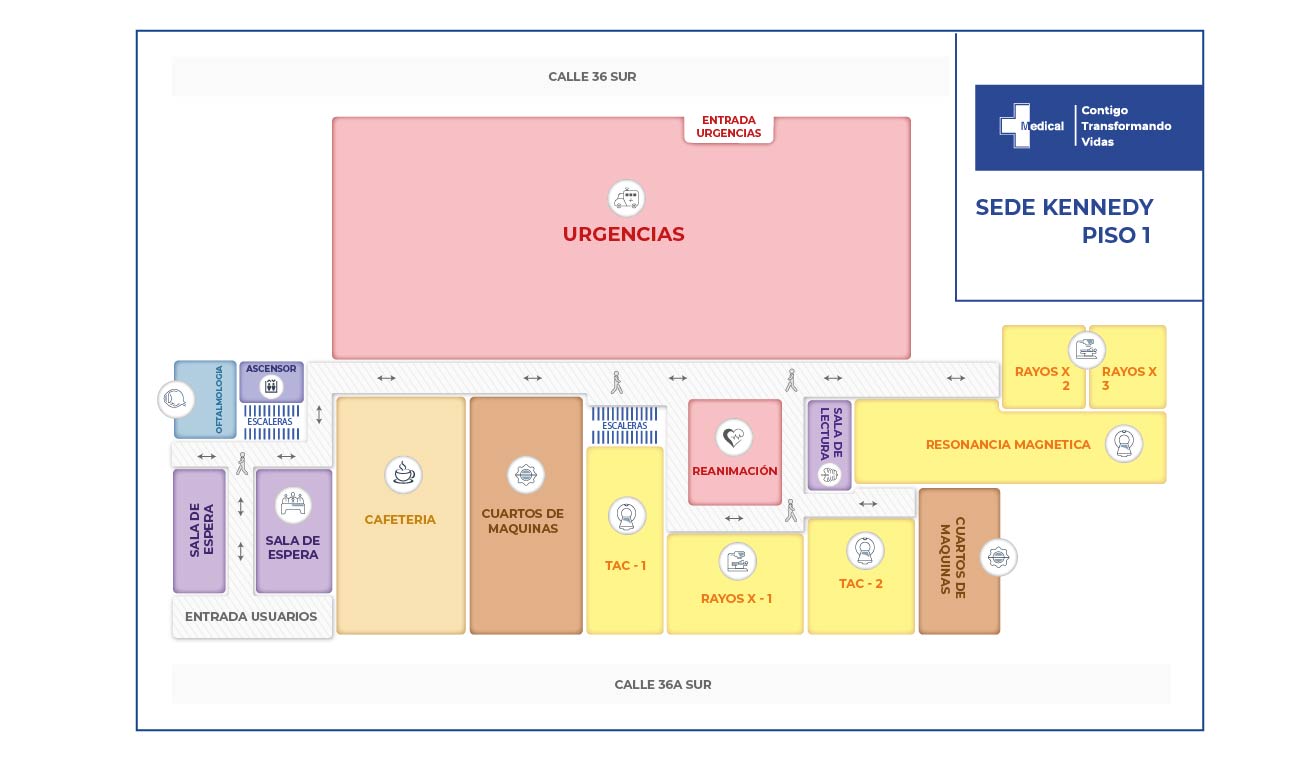

La condición de ingreso es realmente poco alentadora, sin embargo la oportunidad de los servicios, la eficiencia y eficacia que caracteriza a la clínica Medical SAS, ofrece al paciente y su familia todo un equipo interdisciplinario para la atención adecuada y secuencial para este tipo de traumas. Precedida por especialistas en cirugía general, neurocirugía, psicología, psiquiatría, servicios de apoyo terapéutico y radiológico, salas de cirugía, unidad de cuidados intensivos, rehabilitación física, clínica de heridas, entre otros.